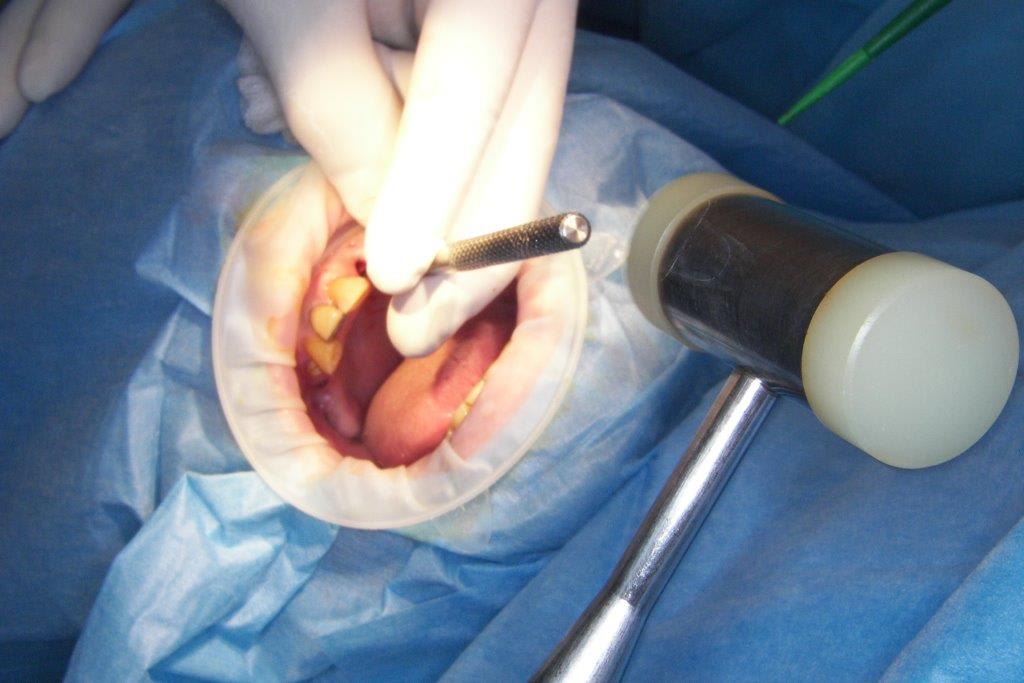

pour ceux que ça intéressent, une petite utilisation d'expansion de la paroi palatine, sur une avulsion d’incisive(racine fendue). toutes mes excuses pour la mauvaise qualité des photos.

Et à ton avis pourquoi ton incisive s'est fendue ? Y a qu'à regarder ta photo ...

Et donc tu mets un Implant dans ce contexte là .... faudra pas se demander pourquoi il y aura des complications prothétiques de type fracture de vis